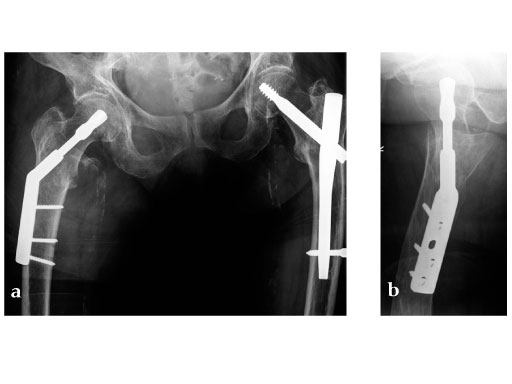

With the applied loading regime a total of 100% cut-outs occurred in the DHS group compared to 50% in the DHS blade group. The survival probability in terms of cut-out resistance was significantly higher for the DHS blade (Fig 2) (P=.023).

Based on the data available, we conclude that the DHS blade performs superior compared to the DHS in terms of cut-out resistance under cyclic loading. This might be due to cancellous bone compaction around the helical blade during implant insertion (Fig 3), which should be investigated in further studies. This in vitro study supports the usage of the DHS blade in order to reduce the cut-out rate in treatment of unstable femoral neck fractures.

Müller AO Classification type 31-A2 fracture in an 83 year-old female with severe osteoporosis.